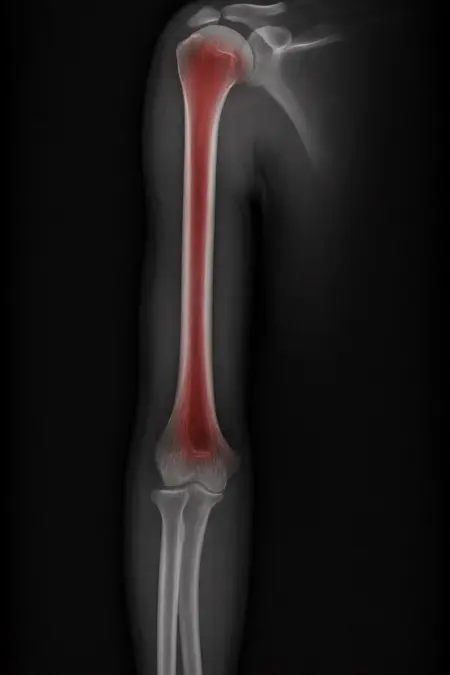

アートや写真の編集用に設計されたFlux Kontextのようなモデルを、医療画像、たとえば「単純な」骨折の赤色マーキングに使用できるか?

即答:面白い結果を出すが、過剰に反応し、医療ツールとしては信頼性に欠ける。これはアイデアを試すためのプロトタイプに過ぎない。

さらに攻撃的な設定(例:rk beta57、Denoise 1.0)では、**偽陽性100%、検出100%**という馬鹿げた結果に:すべてを赤で塗りつぶし、健常部もほぼすべて骨折と誤認する。未経験の目には区別がつかない。

有効な用途

- 医療画像におけるAIプロトタイプやテスト

- X線の「疑わしい」領域を視覚的に目立たせる(実験的・創造的アート、エキゾチックなツール xD)

- 感度 vs 偽陽性のバランスを実験するための教育的・実験的素材